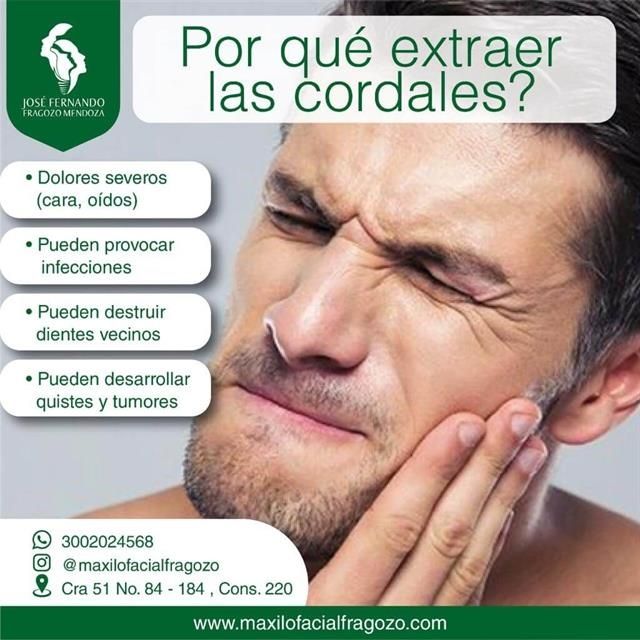

Procedimientos y tratamientos:

Recomendado 100% me realice la cirugía de cordales, cero dolor Una excelente atención, poca inflamación y rápida recuperación.

Excelente cirujano 100% se los recomiendo pues me saque dos cordales y no hubo dolor en el procedimiento y una rápida recuperación ??

Tiene buena mano el Dr. La extracción de cordales fue sin dolor. Buena recuperación.